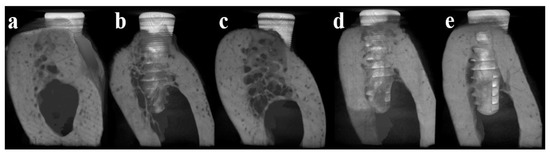

3.4.3. Micro Computed Tomography (μCT)

3.4.4. Histomorphometric Analysis